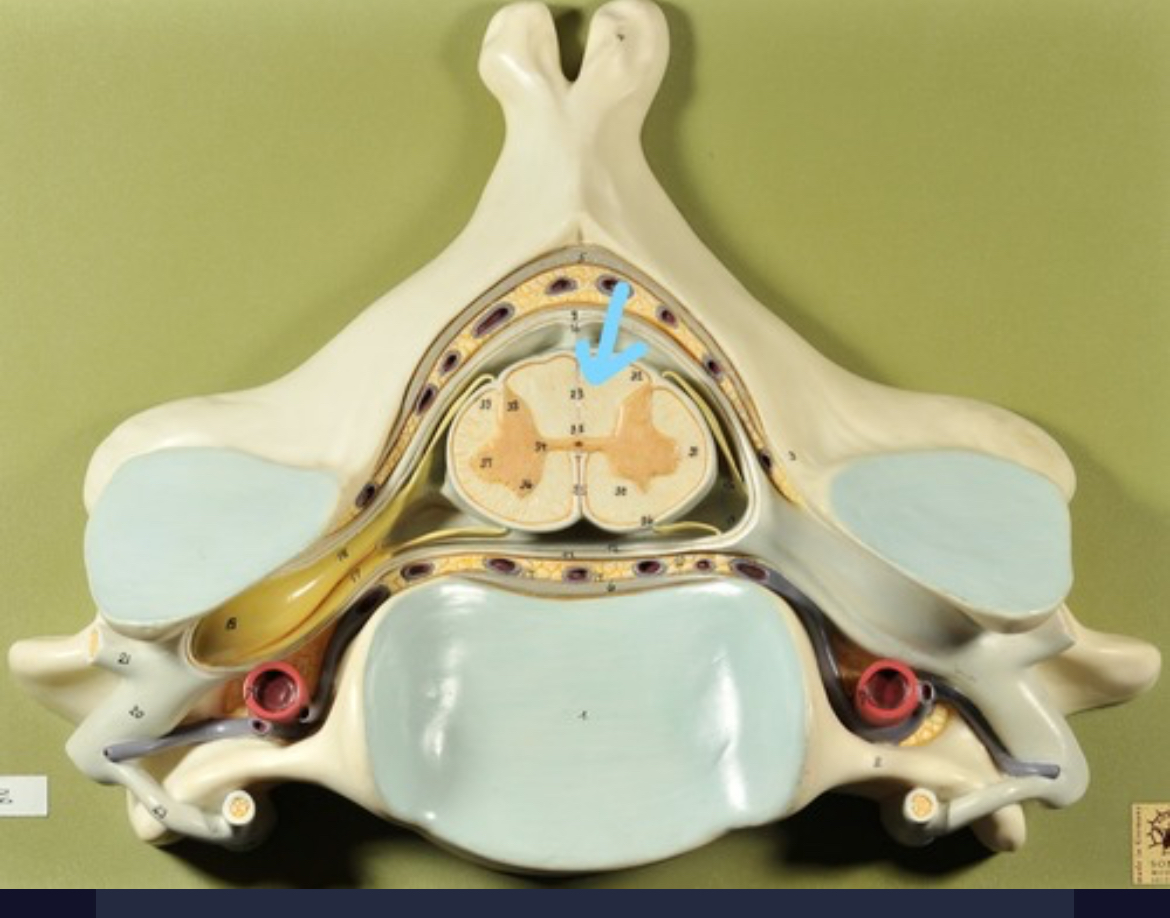

Dura mater (outermost layer)

White matter of spinal cord

Gray matter of spinal cord

Ventral horns (of gray matter)

Dorsal horns

Anterior columns of white matter

Lateral columns of white matter

Posterior columns of white matter

central canal of spinal cord

Pia matter

Subarachnoid space

Arachnoid matter

Subdural space (brown line)

Dura matter

Epidural space

Dorsal root ganglion

Dorsal root

Ventral root

Spinal nerve